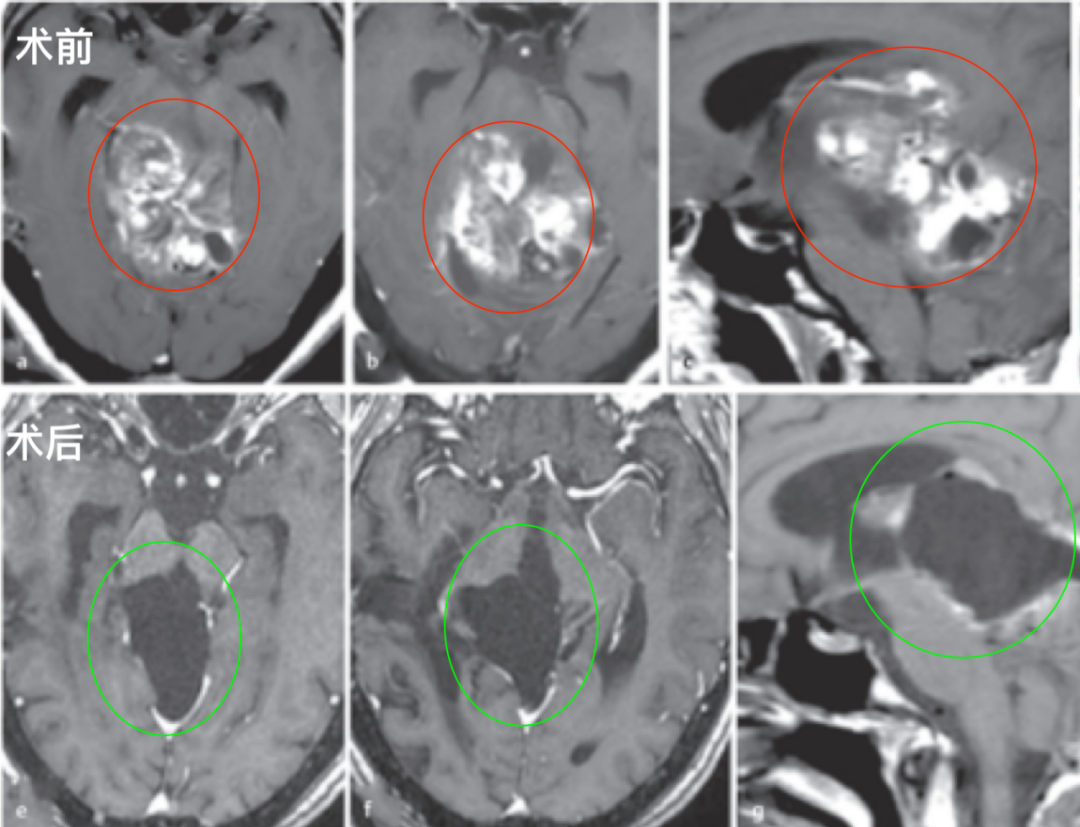

年僅2歲的兒子,從確診膠質(zhì)瘤到順利開顱手術(shù),每一步我們都是怎么走過來的?

孩子生病,做父母的沒有不心疼的!2歲的托馬斯一直是全家人的開心果,活潑可愛,誰會(huì)把腦瘤和他聯(lián)系起來呢? 孩子偶爾頭疼發(fā)熱是常事,但這次完全不一樣。病情來得又急又猛托馬斯突然...